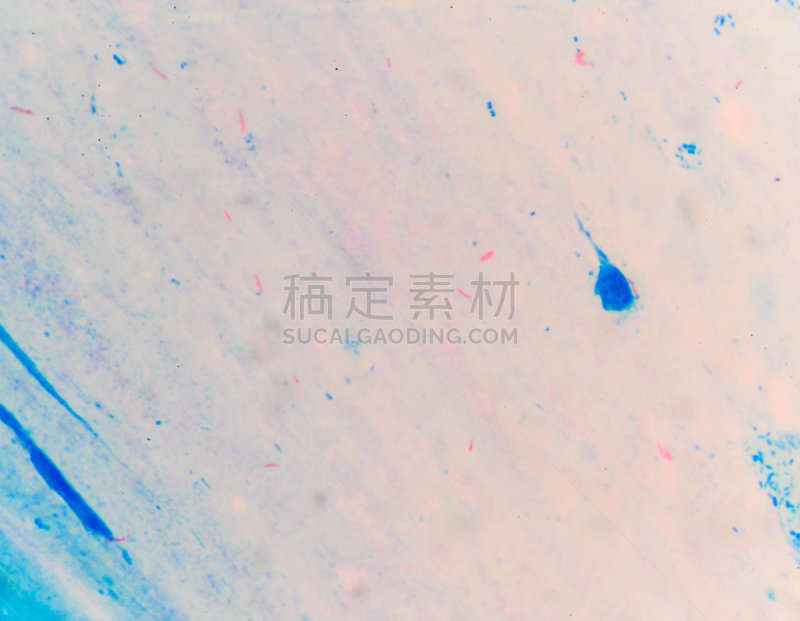

革兰氏染色剂详情

JPG